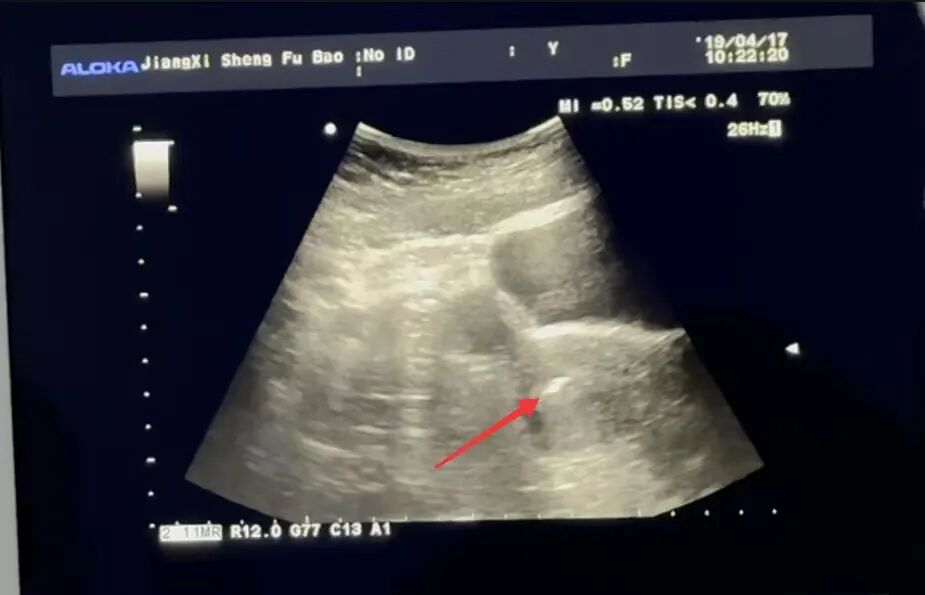

医生在B超引导下,用细软移植管将胚胎送入子宫腔:

移植时妈妈在屏幕上可看到一个小白点就是胚胎宝宝被精准放置的地方,整个移植过程无痛,仅需几分钟。